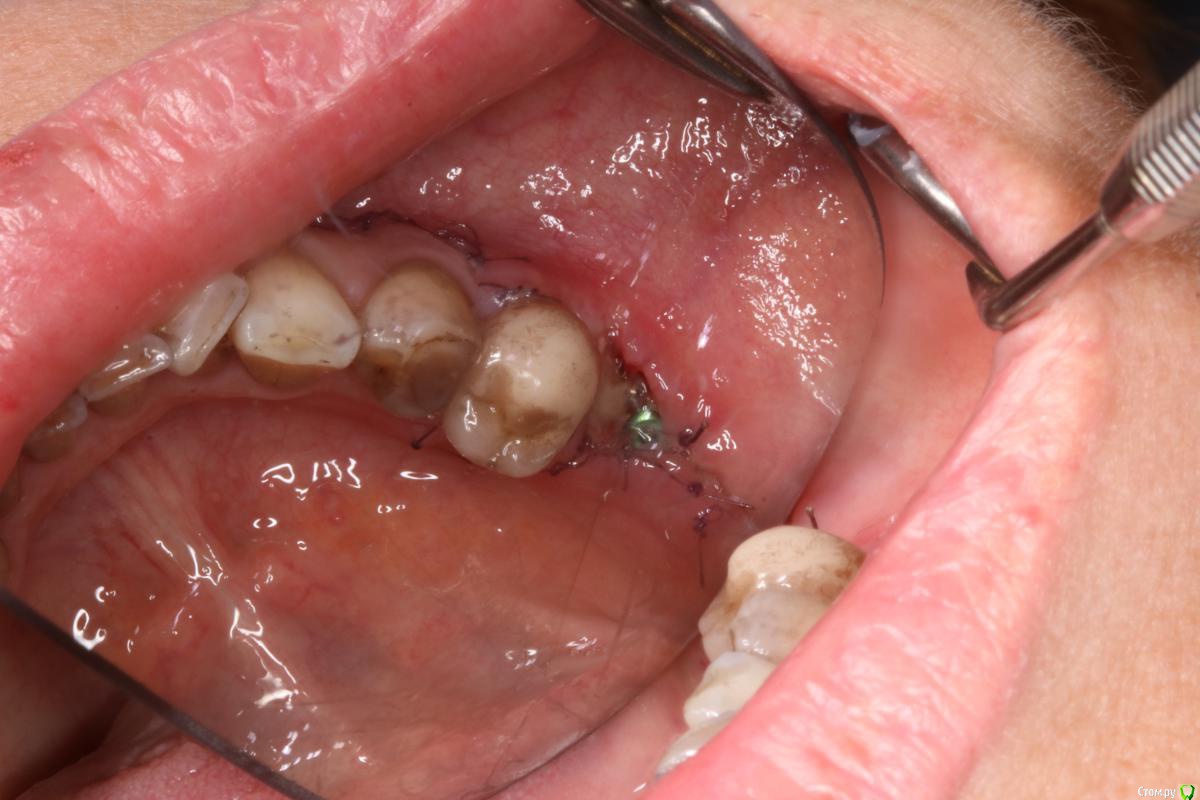

igorgergg Опубликовано 17 июня, 2018 Поделиться Опубликовано 17 июня, 2018 Всем привет, пациентке было сделано нкр в области 36 зуба с необиотековской сеткой. Щечный лоскут плохо натягивался после рассечения надкостницы и тупого прохождения ножницами и язычного отслаивания, пришлось сделать послабляющий между 4 и 5. Но и его не сильно хватило, лоскут язычно натягивался всего на 0.5 см где-то, чувствовал что натяжение есть.Хотя раньше, когда мобилизовался, хватало обычного рассечение надкостницы и язычно отслаиться. В итоге сетка прорезалась, но мне кажется есть и вторая причина почему, так как возможно на сетке были углы острые поэтому и не затянулась. Ушивался 2-3 П- образных и сверху простые узловые наглухо. Фото прилагаю. Сейчас хочу с мембраной эволюшен переделать, но есть опасения что причина также и в натяжении после ушивания, так как даже с послабляющим я не смог натянуть без натяжения лоскут. Также сейчас слизистая в этом месте подвижная и тонкая стала, что может усложнить операцию и ушивание. Чтобы был успех исключаю титановую сетку и вопрос в ушивании и также вопрос может пластику десны первым этапом сделать в такой ситуации (смещенным лоскутом с трансплантатом?), так как на этом месте сейчас щека натянута, на фото видно. Дайте плз обратную связь) Опыт есть, но его не так много Ссылка на комментарий

igorgergg Опубликовано 22 июня, 2018 Автор Поделиться Опубликовано 22 июня, 2018 Что за Pt на семёрке ?Тут с Эволюшн +2мм кости вестибулярного получить достаточно. Зачем сетки ?Имплант сразу.семерку удалили уже смущает тонкий биотип, думаю что сложно будет ушиться. в области пятеркки также прикрепенки не стало после нкр Ссылка на комментарий